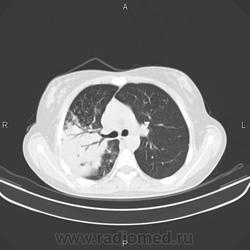

Задействован весь сегмент S2 справа. Полость деструкции. Перисциссурит. Можно сказать, ограничено со всех сторон плеврой. Мелкоочаговие высоко- и среднеинтенсвные тени в S1, S3 и S6 - отсев. Симптом позитивной воздушной бронхограммы. Объективных данных мало, но это инфильтративный туберкулёз сегмента S2 правого легкого в фазе распада и дессименации.

Спасибо всем ещё раз. Описывая КТ нашел ещё отсев в S1,3,6,10 правого легкого и S3,6 левого легкого. Так что туб этиология вызывает все меньше сомнений.

Больше данных за инфильтративный туберкулёз с распадом и обсеменением, но всё-таки абссцедирующую пневмонию из диф.ряда я бы не убирал, т.к. ни в одном из очагов не вижу признаков пресловутого казеоза( вкраплений извести).Было бы хорошо, если бы вы предствили R-граммы 2-недельной давности, кстати отсутствие по ним динамики, на фоне антибактериального лечения ещё не доказывает туберкулёзный процесс, т.к. есть пневмонии с затяжным течением и может быть прогрессирование пневмонии на фоне лечения. Необходима консультация фтизиатра.

уплотнение в верхней доле с распадом, односторонними ценрилобулярными узелками,без поражения левого легкого-сомнительно сразу писать tbc,включить бронхиолит,атипичную пневмонию,грибковое поражение (аспергиллез) в д.д ряд